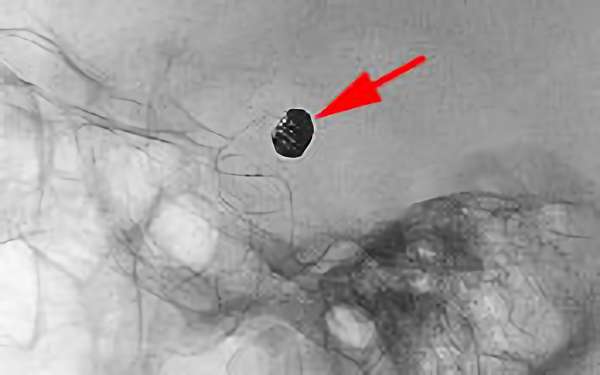

No.1631 手術後